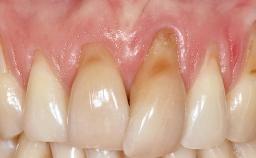

Early Implant Placement, Contour Augmentation, and Autologous Connective-Tissue Graft Using a Tunneling Technique to Replace an Upper Incisor with Generalized Gingival Recession

Variations in soft-tissue volume, evidenced either by an overabundance (Evian and coworkers 1993; Levine and McGuire1997; Dolt and Robbins 1997) or by a deficiency of soft or hard tissue can complicate implant-supported rehabilitations in the esthetic zone (Lorenzana 2008; Lorenzana and coworkers 2009). The present case illustrates the replacement of a failing upper left lateral incisor complicated by generalized severe gingival recession in the esthetic zone.

| Soft Tissue Anatomy | Intact | Defective | |

| Bone Volume | Horizontally and vertically sufficient | Horizontally deficient | Deficient vertically or deficient vertically AND horizontally |